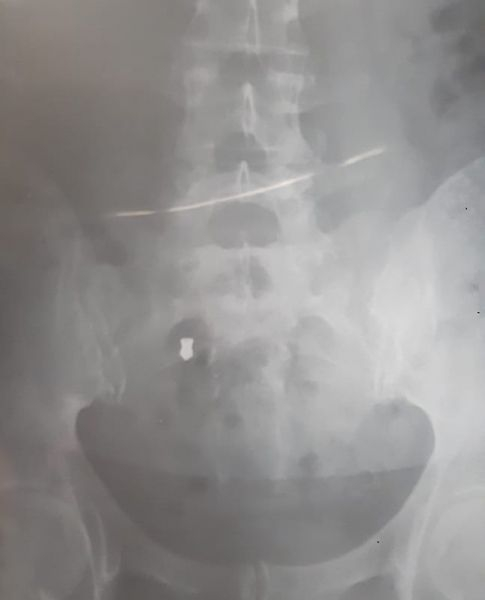

Aquí comença un calvari per a la dona. A l’hospital la van curar amb Betadine, una solució cutània desinfectant de la pell d'ús general, petites ferides i talls superficials. L’endemà i pel seu compte, va poder sotmetre’s a una ecografia que va detectar la presència del perdigó. “Va ser una odissea de metges, de proves...Un metge me’l va intentar treure amb anestèsia local però era impossible perquè estava molt endins. Vaig anar a diversos metges que no em volien operar i el dolor era horrorós. El tenia a la zona lumbar, molt a prop del sacre”.

Al desembre del 2018 li van extreure el perdigó. Va ingressar a una unitat de dolor a Barcelona, medicada amb morfina i lidocaïna - anestèsic local, com a sedant, analgèsic i anticonvulsiu-; sessions de fisioteràpia, infiltracions, bloqueig del nervi sense que hi hagués solució per al dolor amb afectacions neurològiques. “No es pot fer res”, lamenta i afegeix que continuen les dolències.